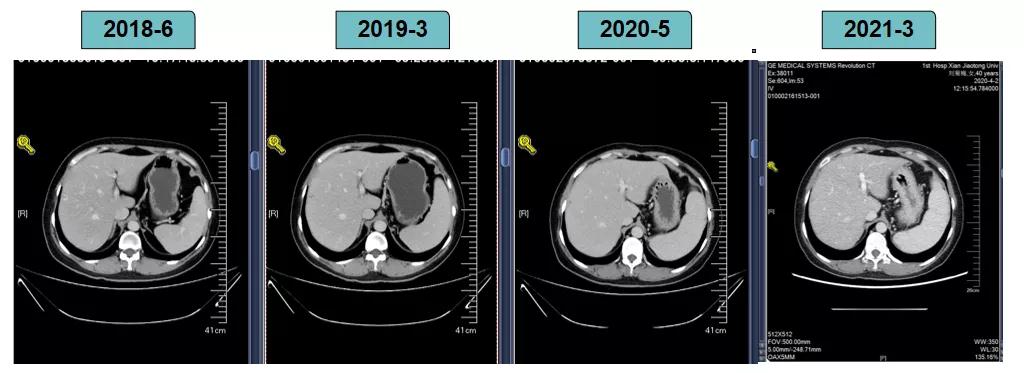

胸腹部增强CT示(2018-6-28):胸骨后占位,肝内异常强化灶,腹膜后肿大淋巴结。

2018-7-17成功入组ELAINA临床研究(试验方案编号:BO29919),IWRS分配随机号3210。于2018-7-17开始接受T-DM1 3.6mg/kg(252mg)治疗,并间断对其进行疗效评估。现阶段患者PFS达近40个月。

靶病灶:腹主动脉左侧和下腔静脉右侧淋巴结

非靶病灶:肝左叶、肝右前叶下段;纵膈胸骨后淋巴结节;前上纵膈淋巴结;腹膜后小淋巴结

影像学评估-肝脏:

影像学评估-腹膜后淋巴结: